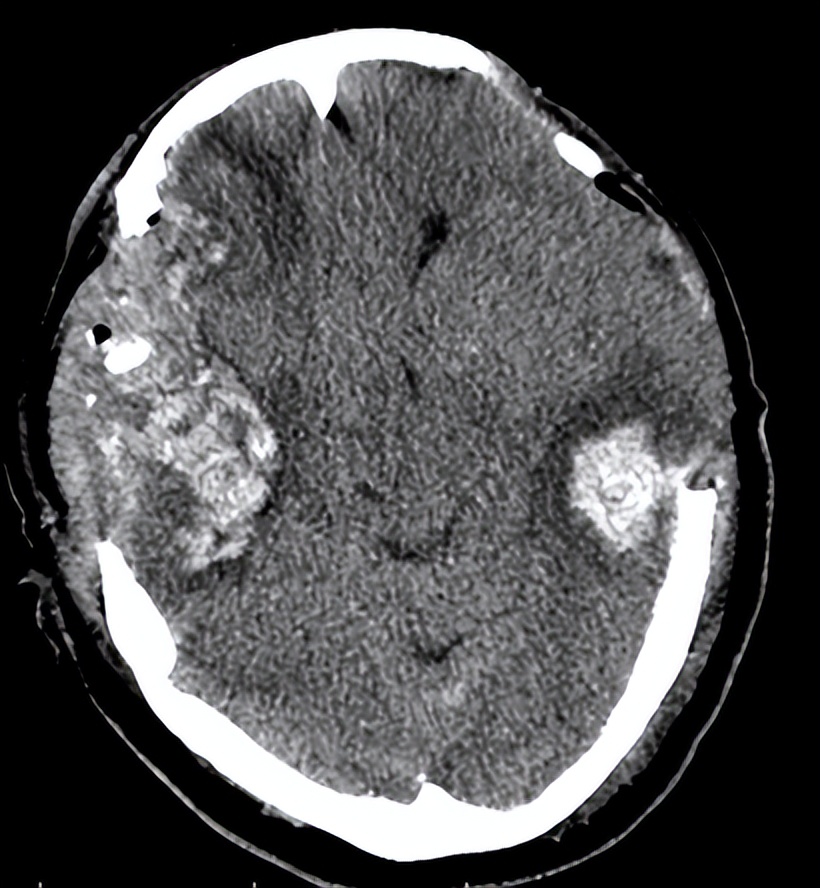

06-08术后第一天复查头CT示:

术后第一天第二天,患者呈昏迷状,反应较前变差,但生命体征平稳。